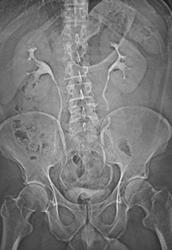

Testicular Cancer